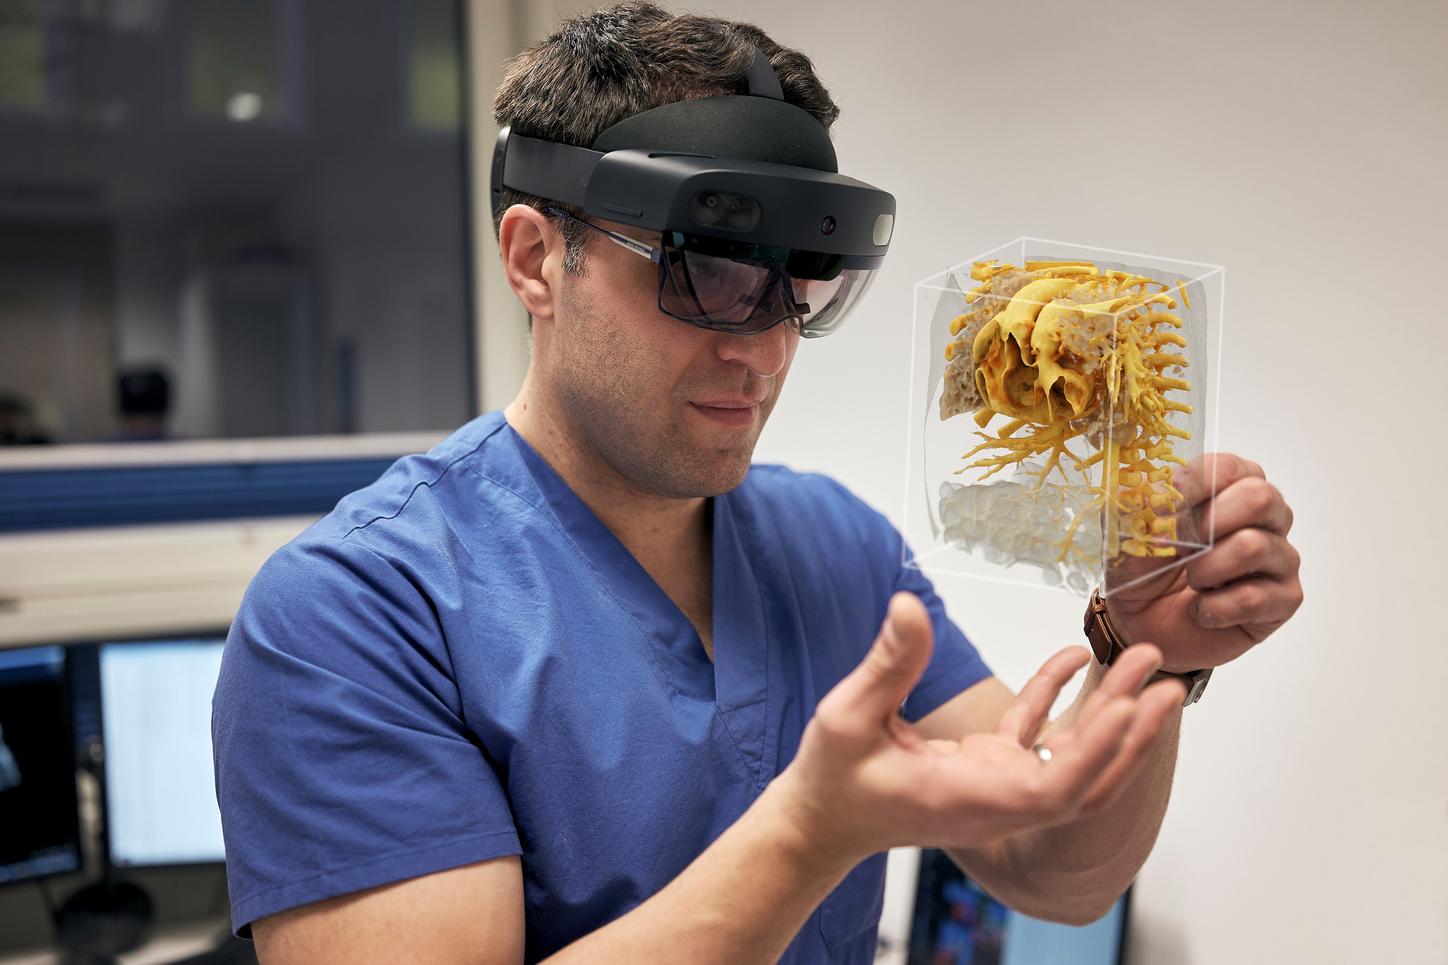

Visualize the smallest structures of the heart realistically without surgery? About the use of a prototype that makes this vision almost tangible.

Cardiac surgery is one of the most difficult procedures, and it gets even more complex when it comes to operating on tiny children’s hearts. Visualization techniques like cinematic rendering provide a detailed 3-D view of the patient’s heart and surrounding anatomy. But what happens when these images are turned into a hologram that can be rotated, zoomed, and looked at from all possible perspectives?

The combination of cVRT and HoloLens 2 is still in a prototype state and not commercially available yet.